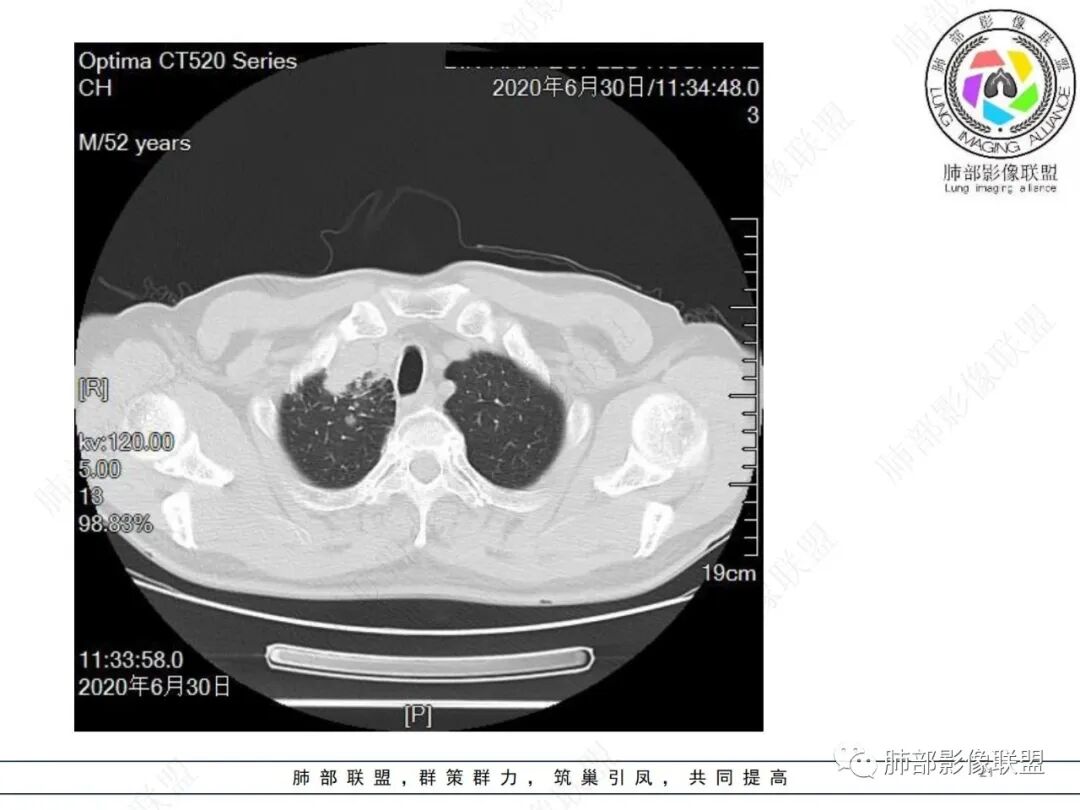

中年男性,有长期吸烟史,右肺上叶不规则肿块,边缘膨隆有分叶,支气管截断,不均匀强化,内有多灶性坏死,癌胚抗原升高,考虑肺癌可能性大,鳞癌可能。鉴别腺癌。

右肺上叶不规则形软组织密度肿块影,边缘见分叶,毛刺,病灶呈宽基底与胸膜相连,病灶内见坏死,增强扫描呈不均匀性强化,右肺上叶支气管截断,纵隔内见肿大淋巴结,肿瘤标志物增高,考虑鳞癌可能,鉴别小细胞癌,腺癌。

右肺上叶不规则肿块,分叶、毛刺,上叶支气管截断,断端圆钝,不均匀强化,其内空泡及坏死,坏死边界不清,考虑腺癌或腺鳞癌,鉴别鳞癌

中年男性,长期吸烟,CT示右肺上叶肿块影,有分叶,毛刺,胸膜牵拉,支气管截断,边缘斑片影,病变内有坏死,强化,淋巴结肿大,首先考虑鳞癌可能性大,鉴别腺鳞癌

除了年龄,吸烟,湖泊样坏死符合鳞癌,其他都不符合,支气管截断,不在肿块中央,远处也没有明显阻塞样改变,更像爬行后截断,肿瘤标志物CEA高得厉害,其他鳞癌标志物并不高。这种坏死,低分化腺癌一样常见,强化远端也有强化,不符合鳞癌,所以我考虑低分化腺癌(伴或不伴有神经内分泌分化)或者肉瘤样癌。

边缘都是强化的肿瘤组织,鳞癌是不会这样的,符合腺癌

不符合鳞癌有四点:1,截断的支气管不在肿块中央,而是外朝内爬行(肿块外缘大于近端)2、支气管截断在前段,前段远端没有阻塞性改变。3、鳞癌是近端强化,远端为阻塞性的不强化粘液栓或明显强化的不张肺组织,这个是中间坏死,周围强化的肿瘤组织。4、肿瘤标志物CEA增高太明显,鳞癌标志物不高。